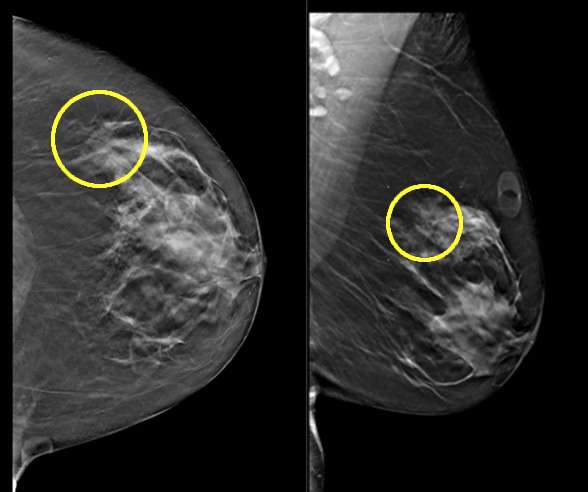

The imaging appearance of ALH is non-specific, with significant overlap when compared to other suspicious and malignant lesions within the breast. On mammography, the most common presentation of ALH is calcification (60-90% of cases), most often pleomorphic, followed by amorphous and coarse heterogeneous calcifications. Architectural distortion and masses are also seen in association with ALH, though less common.4